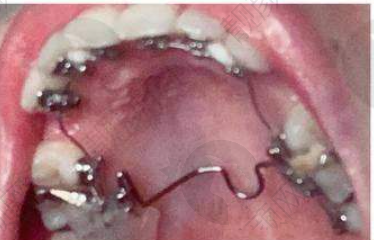

孔卫东医生舌侧隐形矫正实例

曾经有一位成年患者,牙齿排列不齐,存在重度的错颌畸形问题,对美观和咀嚼功能都造成了较大影响。患者尝试过多种矫正方法,但成效都不理想。后来找到了孔卫东医生,孔医生为他进行了详细的检查和评估,决定采用舌侧隐形矫正技术。在矫正过程中,孔医生根据患者牙齿的移动情况,及时调整矫正方案。经过一段时间的矫正,患者的牙齿逐渐变得整齐,面部美观度也得到了明显提升。患者对矫正成效非常满意,重拾了自信。